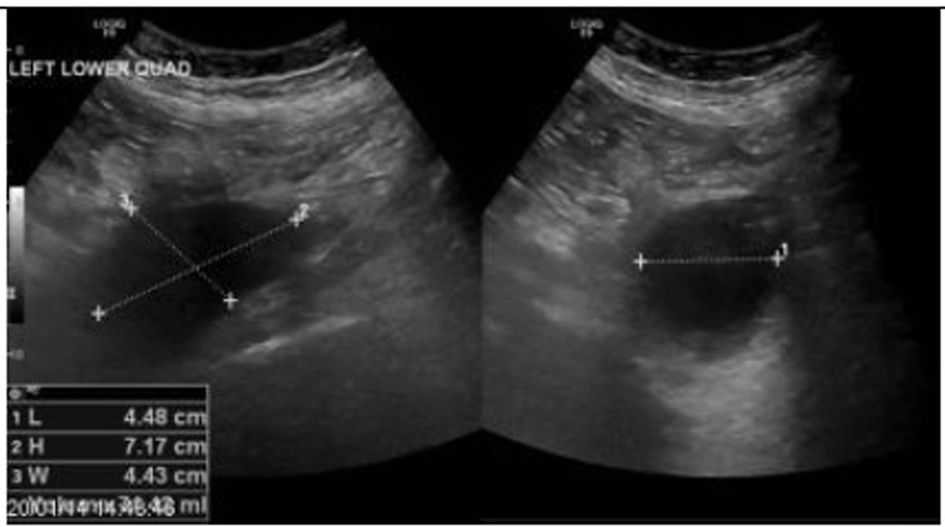

A 64-year-old man with prostate cancer, bone metastasis and coagulation disorder presented with abdominal distension. He underwent abdomen and pelvis ultrasound for assessment of ascitis, which showed localized fluid collections identified at the left iliac fossa with volume approximately 74 mL and right iliac fossa with volume approximately 48 mL (Fig. 1, 2).

![]() Click for large image | Figure 1. A localized fluid collection indentified at left iliac fossa with volume approximately 74 mL. |